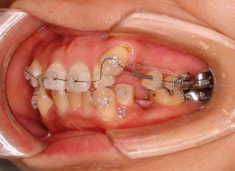

治療開始から約1年2ヶ月後